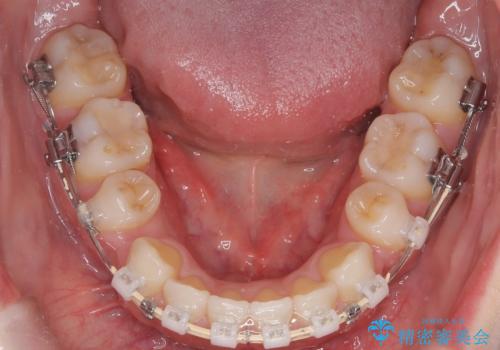

上下4本の抜歯と審美ワイヤー矯正で整った歯並びへ

- 患者様は、歯並びの乱れを整えたいとのことで来院されました。診察の結果、歯列のスペース不足が原因で前歯のガタつきが目立ち、噛み合わせにも影響が出ている状態でした。歯を正しく並べるためにはスペースの確保が必要と判断し、上下の小臼歯4本を抜歯して、審美ワイヤー矯正(白いワイヤーと透明ブラケット)で治療を行う計画を立てました。

まず、抜歯によって歯を動かすためのスペースを確保。その後、審美ワイヤー矯正を用いて、前歯のガタつきを整えながら、噛み合わせの調整も行いました。審美装置を使用することで、矯正中も目立ちにくく、自然な仕上がりを目指して治療を進めました。治療の結果、歯並びがきれいに整い、口元のバランスも改善しました。患者様からは「歯並びがきれいになり、自信を持って笑えるようになった」と喜びの声をいただきました。